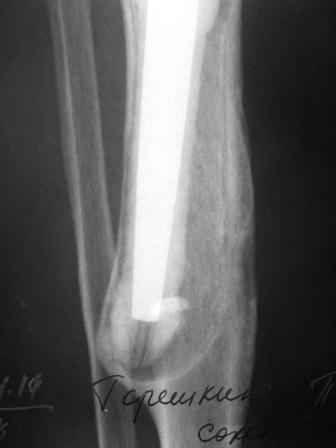

Уважаемые коллеги!Хотелось бы услышать Ваше мнение о возможности и способе помощи больной. 1939 г.р. В 1995г. эндопротезирование правого коленного сустава протезом Феникс, в 1999г. в г. Томске - ревизия - ротационный хинч W.Link. C 2005г. прогрессирует варусная деформация за счетнестабильности тибиального компонента. Попытка ортезирования - без эффекта. Попытка направить в ФСМУ без эффекта, да и больная не хочет никуда ехать.С уважением, Leonid

Понятно что для решения на операцию артродеза необходимы веские причины. Но я не уверен что здесь асептическое расшатывание. Судя по снимкам, бедренный компонент стоит не плохо, и есть рассасывание костной ткани вокруг всего протеза в голени. Что-то мне подсказывает об инфекционном процессе, возможно вялотекущем. В наших условиях я сделал бы обследование включающее анализы крови с СОЭ, СРБ. Сделал бы пункцию коленного сустава или даже биопсию мягких тканей для посева и микроскопии.